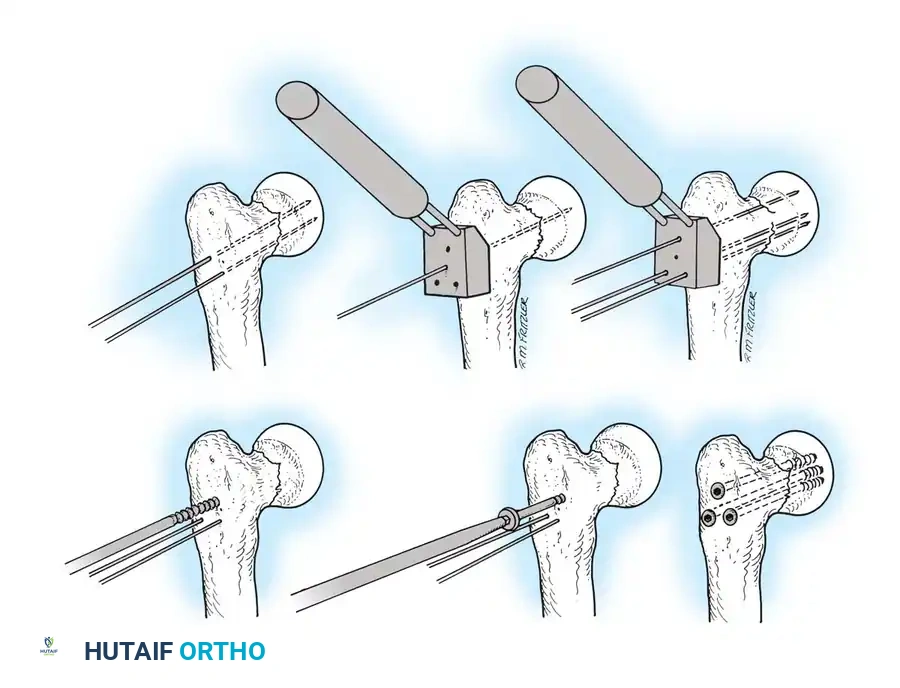

5. Intramedullary Nailing (For Unstable Fractures)

If a cephalomedullary nail is chosen, the entry point is established at the tip of the greater trochanter (or slightly medial, depending on the specific implant design).

Insertion of the cephalomedullary nail down the femoral shaft. Care must be taken not to distract the fracture site during insertion.

After the nail is seated, the proximal lag screw(s) are inserted through the nail into the femoral head, adhering to the same TAD principles.

Proximal locking of the cephalomedullary nail. The targeting guide ensures accurate trajectory into the femoral neck.

Finally, distal locking screws are placed to control rotation and maintain length.

Final fluoroscopic evaluation confirming anatomical reduction, optimal implant placement, and restoration of the neck-shaft angle.